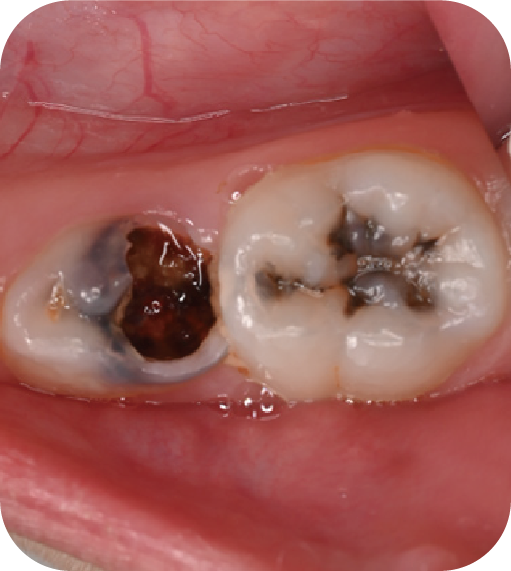

后磨牙,也就是大牙咬合面上凹凸不平的裂隙,這就是“窩溝”。窩溝有很多形狀,有的是狹長的裂隙形狀,還有的在牙齒深處又會分成幾條小溝。這些地方用牙刷很難深入清潔,于是就成了衛生死角,細菌特別喜歡在里面生存,不斷產酸腐蝕牙齒,蛀牙就這樣產生了。如果我們用窩溝封閉把這些衛生死角封起來,那既可以杜絕食物和細菌進入窩溝內,也可以讓窩溝處的清潔變得更簡單,這就是做窩溝封閉的目的。同時它也是世界衛生組織、國家衛健委都推薦的防齲方法。